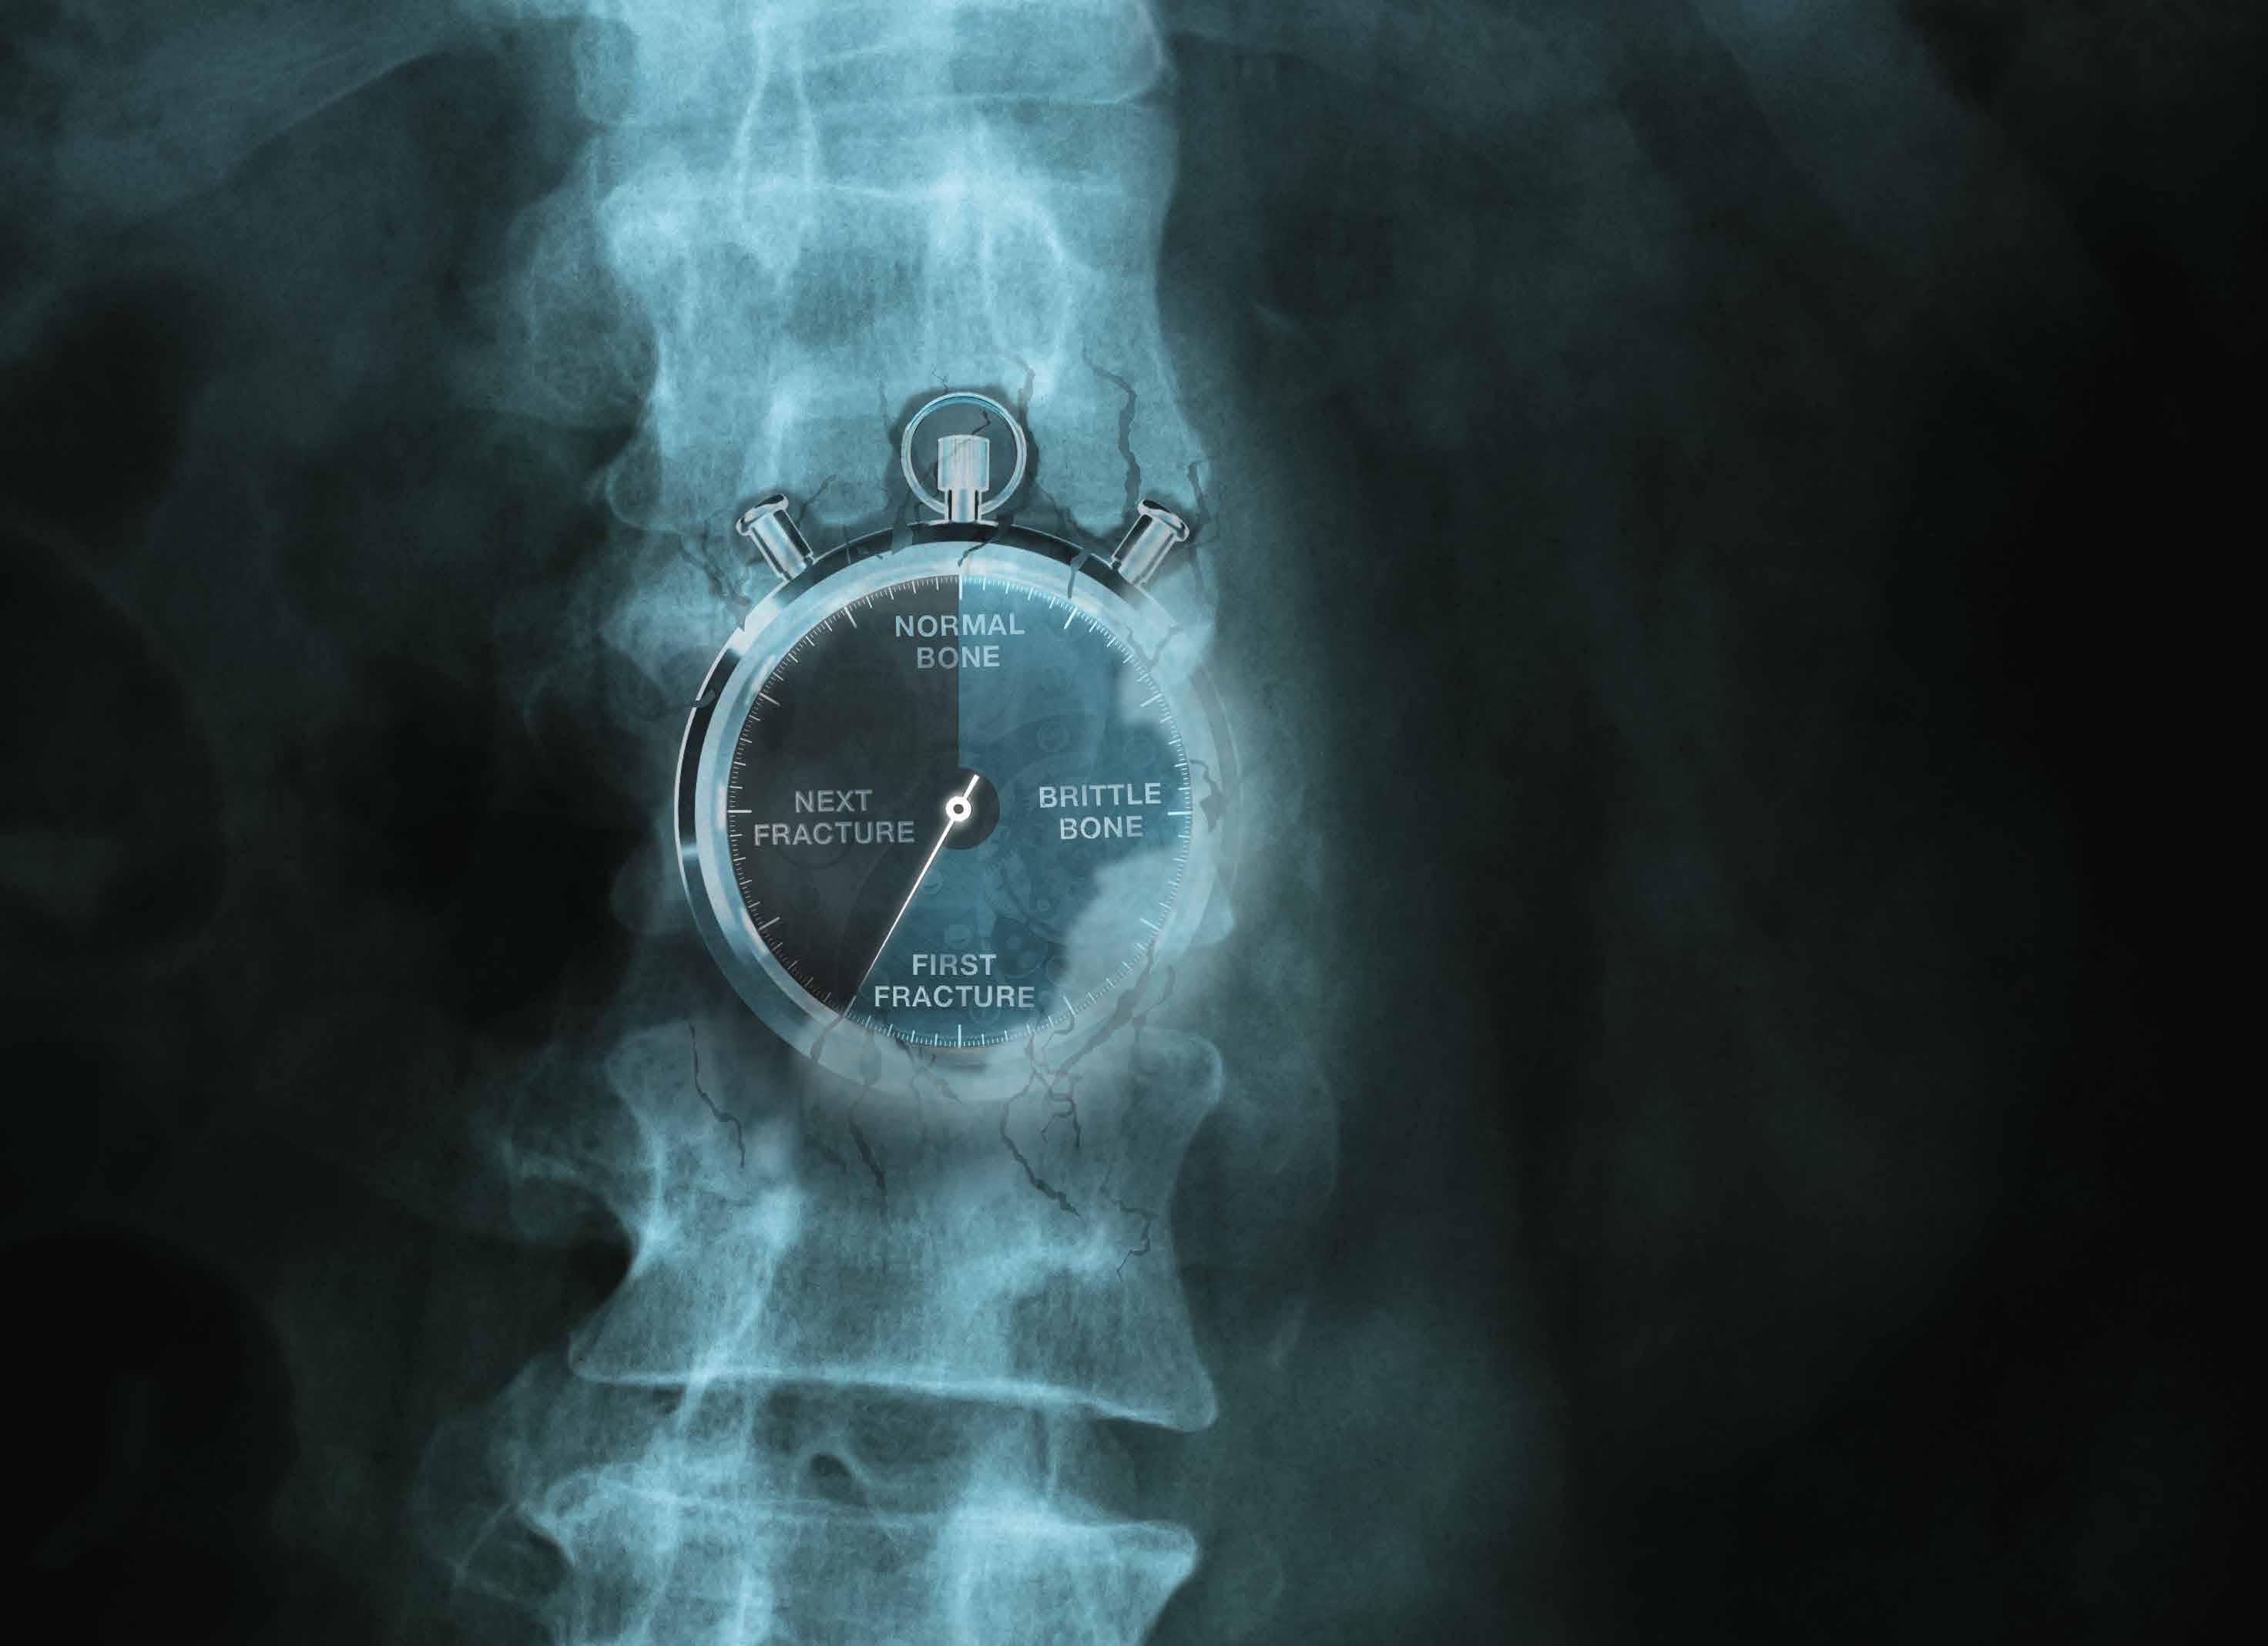

Vitamin D is needed for absorption of calcium and for normal bone and immune health. Vitamin D deficiency can result in softening of the bones and increase the risk of osteoporosis. Vitamin D is made by our skin after sunlight exposure, though in Ireland none can be made from about Halloween to St Patrick’s day, increasing the risk of deficiency. Of concern, food sources of vitamin D are very limited and not commonly eaten; these include oily fish, egg yolk and specific fortified foods such as fortified milk and breakfast cereals.

Currently 300,000 people in Ireland have osteoporosis (according to the Irish Osteoporosis Society), ensuring adequate vitamin D intake in early life can decrease the risk of osteoporosis/ fractures in later life.